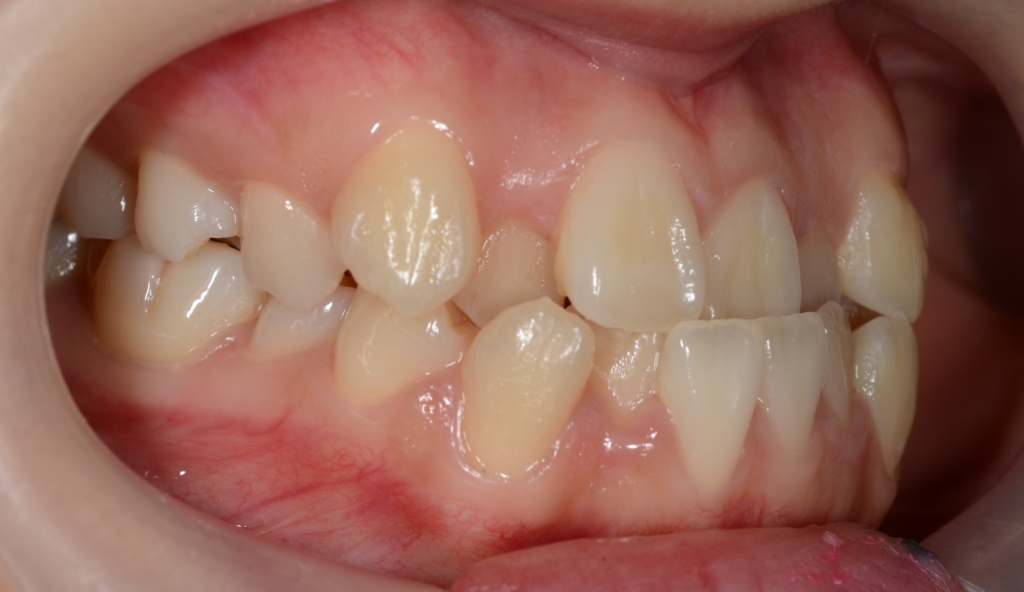

受け口と前歯の凸凹を治したい

「八重歯などのガタガタを治してきれいな歯並びになりたい!」

#1.顎と歯の不調和による叢生

(前歯部の反対咬合を伴う)

#2.骨格的に下顎前突(受け口)傾向